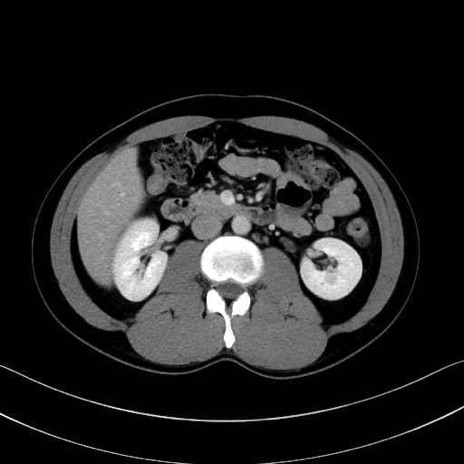

【症例】20歳代 男性 スクリーニング

脾動脈の画像解剖

■起始:典型的には腹腔動脈幹(celiac trunk)から左胃動脈・総肝動脈とともに三分岐し、脾動脈は左後上方へ向かう。

■走行:膵上縁または膵実質背側を蛇行しながら左方へ進み、膵尾部近傍で脾門へ至る。蛇行の程度は個体差が大きい。

■終枝:脾門部で複数の終末枝に分かれ、上極・下極枝や脾門枝群を形成する。胃短動脈群や左胃大網動脈はしばしば脾動脈から分岐する。